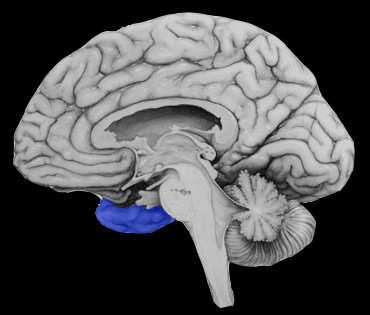

Territoire de l’artère cérébrale moyenne